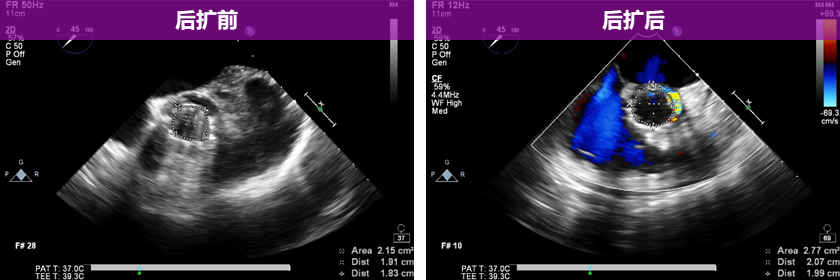

超声影像:

20mm球囊后扩后支架腰部形态接近理想膨胀状态,瓣周漏微量。

植入后血流动力学有效改善,术后Vmean 1.06m/s Pgmean 6mmHg。

在术中面临的一个艰难的抉择:瓣膜释放后位置虽然理想,但造影和超声均显示2点及11点瓣周漏偏多,原本常规选择后扩张,但本例植入烟囱支架,后扩时瓣叶会不会进一步挤压烟囱支架闭塞?不后扩患者预后又难以保障。在这两难的局面下,我们依据术前3D打印的模型在20mm球囊扩张时左冠窦仍有缝隙,决定使用20mm球囊进行后扩,并与冠脉支架球囊对吻扩张,扩张结果瓣周漏明显减少为少量,瓣口面积从2.1cm2增大至2.7cm2。